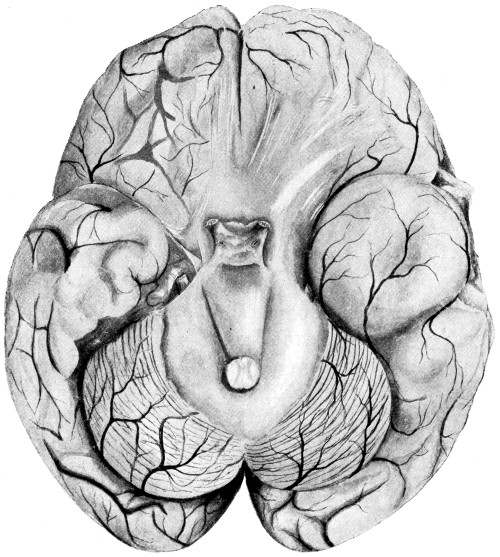

| 62. A glioma of the brain | 211 |

| 63. A sarcoma of the brain | 211 |

| 64. An endothelioma of the dura mater | 212 |

| 65. A fibroma of the dura mater | 212 |

| 66. An acoustic tumour | 213 |

| 67. Symmetrical tuberculomata | 214 |